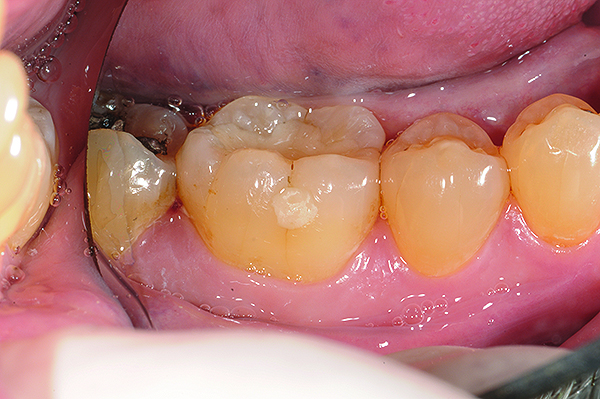

The case depicted in Figure 2 through Figure 5 was completed clinically in late 2009 and subsequently reported in a technique paper published by the author in 2010.37 The case describes the aforementioned EQUIA technique, which essentially employs a high-viscosity, posterior-grade GIC with a bulk-fill technique that is then surface-coated with a penetrating, nanofilled light-cured resin glaze. The reader is referred to the original paper for details about the case, materials, and technique. What is pertinent to this article, however, is the retention and continued durability of the restoration at approximately 42 months. Figure 2 and Figure 3 show the pretreatment view of defective Class I and Class V amalgam restorations, while Figure 4 and Figure 5 illustrate the 42-month recall of the EQUIA Fil restorations. Note that after nearly 4 years of clinical service both restorations were not only still in service but were in excellent condition and would be rated Alfa according to a modified US Public Health Service (USPHS) clinical rating criteria. There is clearly no evidence of excessive wear, staining, marginal microleakage, or recurrent decay. Though this single case is anecdotal, it supports the results found in more comprehensive clinical trials such as those referenced above.

Fig 4 and Fig 5. Occlusal (Fig 4) and buccal (Fig 5) 42-month recall views of the Class I and Class V GIC restorations placed with bulk-fill EQUIA technique.

Figure 4

Figure 5